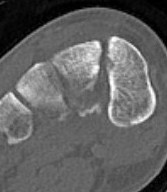

CT

Fleck sign

Fleck sign with inter-cuneiform widening

Dorsal subluxation of the metatarsal